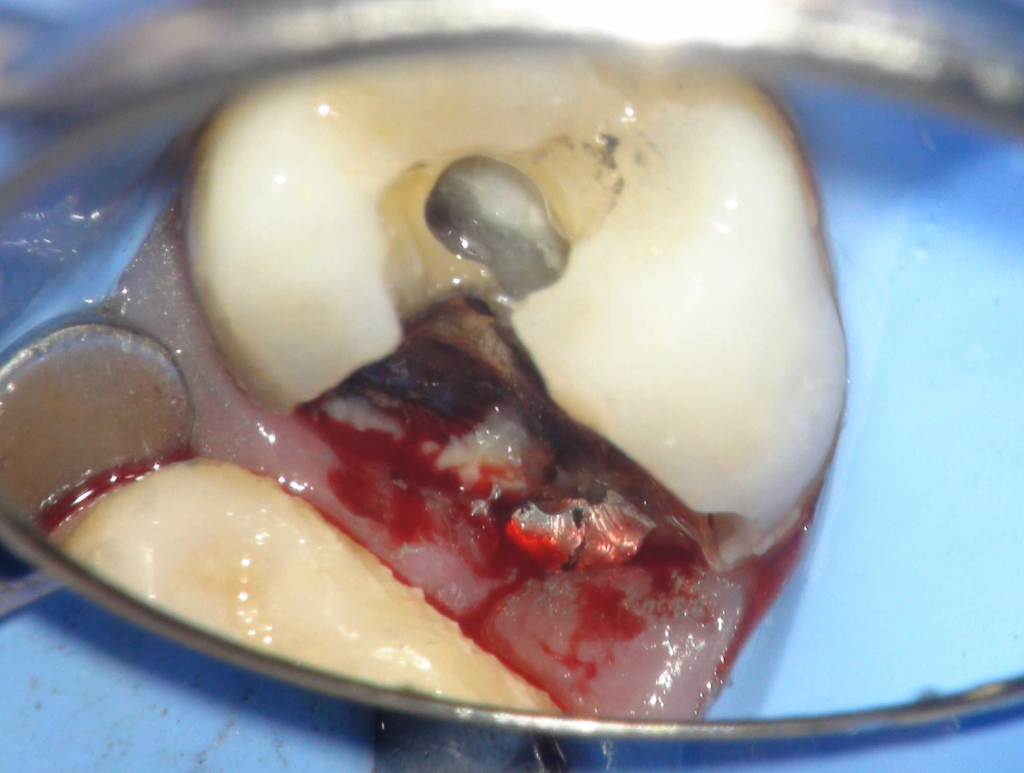

Fisura, remoción amalgama para explorar